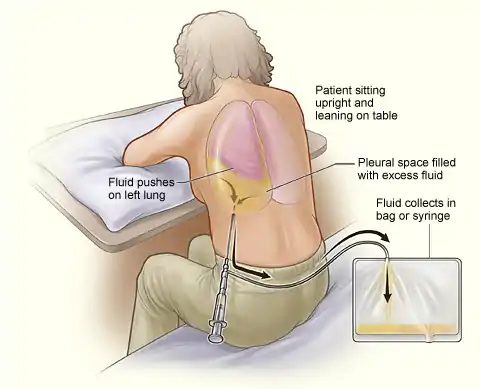

Thoracentesis

Once the presence of an excess fluid in the pleural cavity, or pleural effusion, is suspected and location of fluid is confirmed, a sample of fluid can be removed for testing.[14] The procedure to remove fluid in the chest is called a diagnostic thoracentesis.[15] The doctor inserts a small needle or a thin, hollow, plastic tube in the chest wall and withdraws fluid.[16]

Thoracentesis can be done in the doctor's office or at the hospital. Ultrasound is used to guide the needle to the fluid that is trapped in small pockets around the lungs.

Thoracentesis usually does not cause serious complications. Generally, a chest x-ray is done after the procedure to evaluate the lungs. Possible complications of thoracentesis include the following:

- Bleeding and bruising where the needle went in. In rare cases, bleeding may occur in or around the lung. The doctor can use a chest tube to drain the blood. In some cases, surgery is needed.

- Infection where the needle went in

- Injury to the liver or spleen (in rare cases)

- Pain.

- Pneumothorax, or buildup of air in the pleural space, with a collapsed or partially collapsed lung. Sometimes air comes in through the needle or the needle makes a hole in the lung. Usually, a hole seals itself—but sometimes air builds up around the lung and makes it collapse. A chest tube removes the air and lets the lung expand again.

The lung fluid is examined under a microscope and is evaluated for the presence of chemicals and for its color and texture. The degree of clarity is an indicator of infection, cancer, or other conditions that may be causing the buildup of fluid or blood in the pleural space.

- During thoracentesis, a needle or a thin, hollow, plastic tube is inserted through the ribs in the back of the chest into the chest wall. A syringe is attached to draw fluid out of the chest. This procedure can remove more than 6 cups (1.5 litres) of fluid at a time.